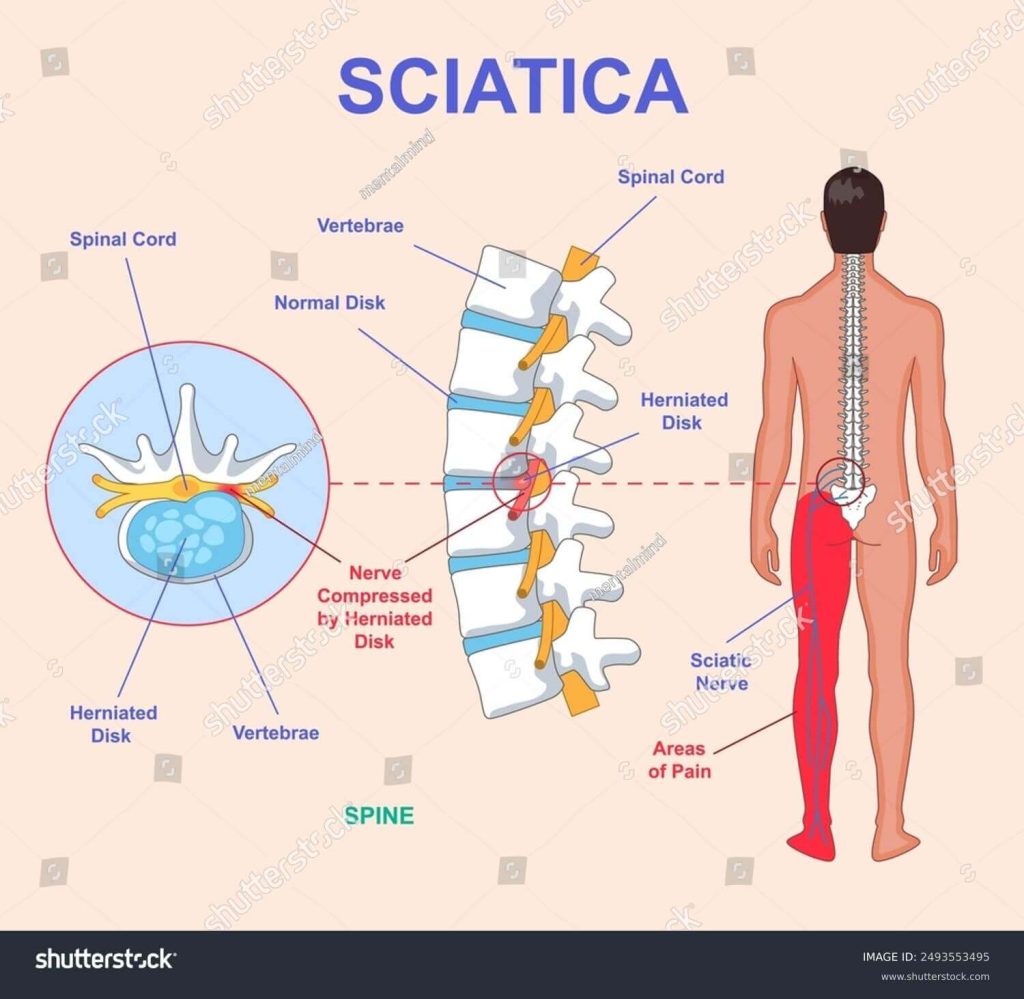

Download Sciatic nerve pain pictures